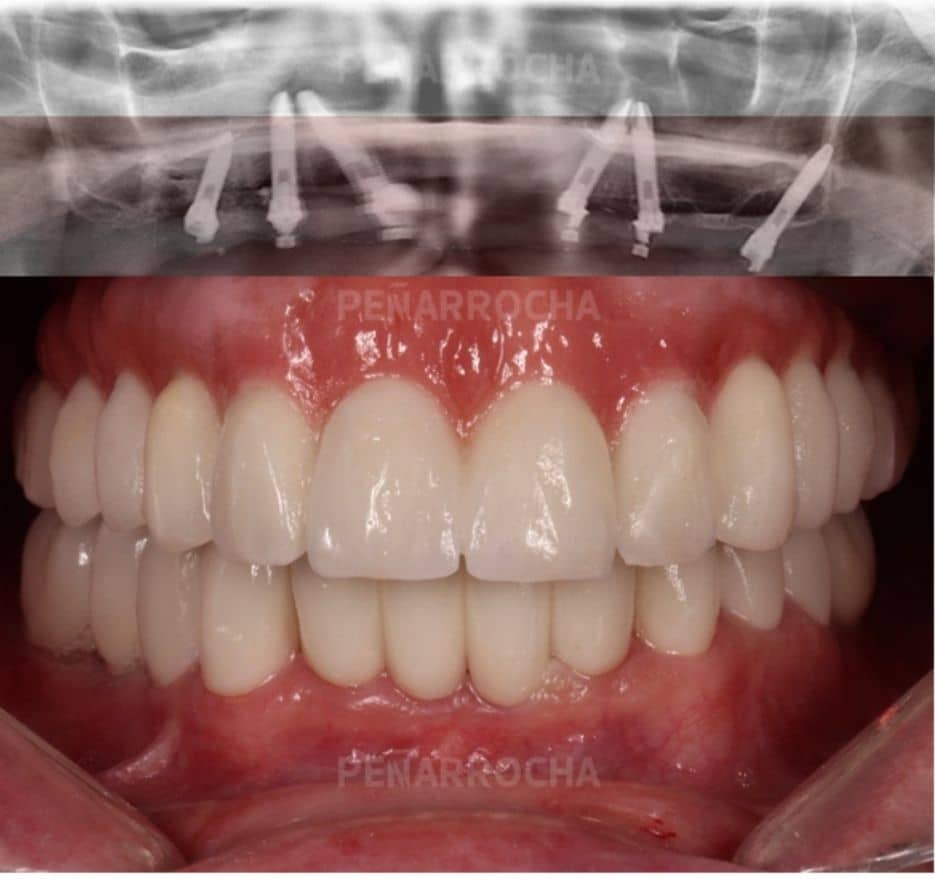

Casos de éxito de implantes dentales con poco hueso en IDIM

En IDIM, contamos con más de 35 años de experiencia tratando casos complejos de implantología dental. A lo largo de nuestra trayectoria hemos logrado recuperar sonrisas de pacientes con condiciones óseas muy complicadas, incluida la falta de hueso suficiente para la colocación de implantes dentales.

Sabemos que la falta de hueso puede ser una preocupación importante, pero gracias a las técnicas avanzadas que utilizamos y a nuestro equipo especializado, hemos logrado devolver a nuestros pacientes no solo una sonrisa estética, sino también una funcionalidad óptima en su boca. Cada paciente es único, y por eso, nos centramos en ofrecer soluciones personalizadas para sus necesidades específicas, teniendo en cuenta la cantidad y calidad del hueso disponible.

Además, entendemos que antes de someterse a un tratamiento tan importante como los implantes dentales, es importante conocer otros casos de pacientes que hayan tenido experiencias satisfactorias. Por eso, a continuación, te compartimos algunos de nuestros casos de éxito más representativos de implantes dentales en pacientes con poco hueso:

Antes:

Después: